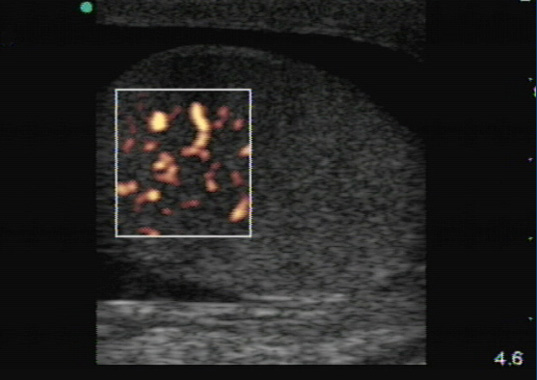

- Standard B-mode is not a reliable method to differentiate between orchitis and testicular torsion. For both orchitis and torsion, inflammation and edema can lead to enlargement and heterogeneous echogenicity of the testis. Color Doppler is helpful to differentiate between orchitis and torsion since blood flow in orchitis is increased in comparison with the unaffected side due to inflammation. 5-7 (Figure 6)

Figure 6. Orchitis. Marked increase in blood flow is seen along with a reactive hydrocele. (Courtesy of Michael Blaivas, MD)